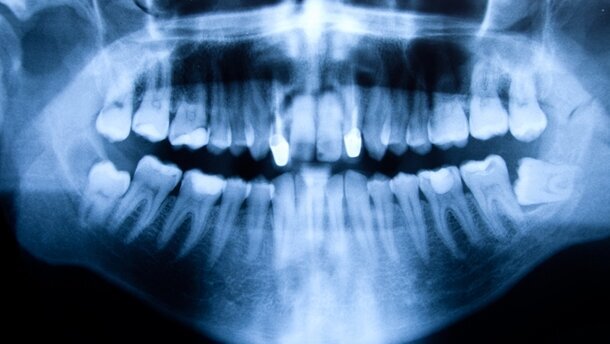

MICHIGAN – Tragbare Geräte mit schmerzlosen Laserstrahlen sollen die Röntgenstrahlen bei der Diagnose von Krankheiten ersetzen.

Wissenschaftler wie Prof. Dr. Michael Morris von der Universität Michigan gehen laut der BBC davon aus, dass die sogenannte Raman-Spektroskopie in rund fünf Jahren bereits allgemein verfügbar sein könnte. Sie soll die Erkennung früher Anzeichen von Brustkrebs, Karies und Osteoporose erleichtern. Mit diesem Verfahren wird die Diagnose von Krankheiten rascher, preiswerter und genauer möglich sein. Die Raman-Spektroskopie beruht auf der Messung der Intensität und der Wellenlänge der Lichtstreuung von Molekülen. Das Verfahren wird bereits in der chemischen und pharmazeutischen Industrie eingesetzt. Prof. Morris untersucht bereits seit einigen Jahren menschliche Knochen mit diesem Verfahren. Er ist davon überzeugt, dass die Raman-Spektroskopie auch bei Patienten/-innen eingesetzt werden kann. Der chemische Aufbau des Gewebes bei einem kranken Menschen unterscheidet sich deutlich von jenem eines Gesunden. Das Raman-Spektrum verändert je nach dem analysierten Gewebe. Daher liefert dieses Verfahren laut Morris einen molekularen Fingerabdruck von dem was gemessen wurde. „Bei Krankheiten ist die chemische Zusammensetzung entweder leicht oder sehr deutlich abweichend. Das hängt von der jeweiligen Krankheit ab“, sagt Prof. Morris. Die Diagnose könnte innerhalb von wenigen Minuten erfolgen, Röntgenstrahlung wird nicht mehr benötigt.